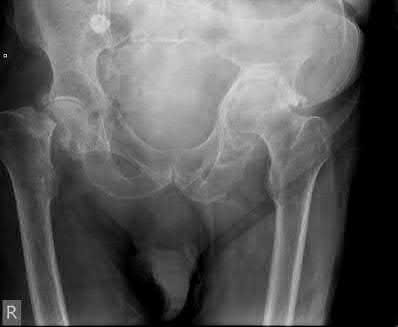

A 45-year-old female sustains a knee injury following a motor vehicle collision. Assuming the representative image demonstrates a medial tibial plateau fracture with articular depression (Schatzker IV), what is the most likely mechanism of injury?

A Schatzker IV fracture involves the medial tibial plateau. The medial plateau is structurally denser and stronger than the lateral plateau, meaning fractures here typically require higher energy. The classic mechanism is a varus force combined with an axial load. In contrast, lateral plateau fractures (Schatzker I-III) are typically caused by a valgus force with an axial load. High-energy trauma to the medial plateau is also highly associated with injury to the peroneal nerve, popliteal artery, and ligamentous structures (like the ACL or LCL).